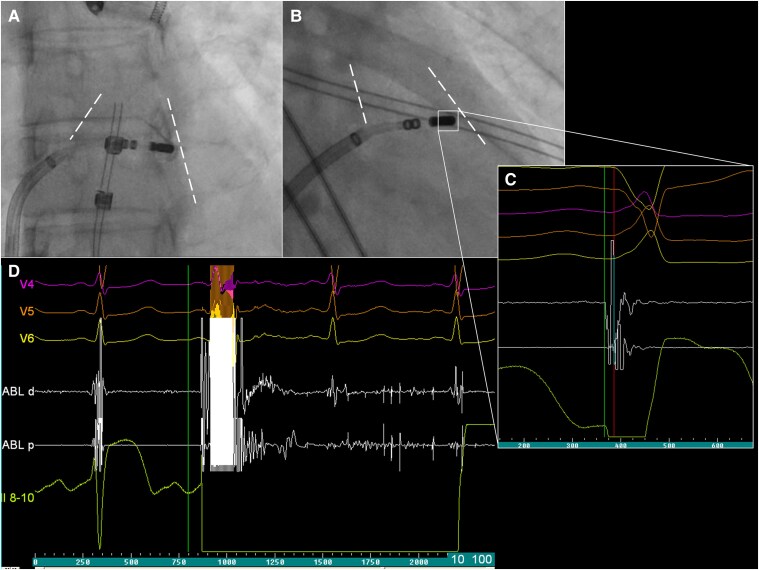

Case summary: A 38-year-old female with highly symptomatic, monomorphic PVCs was referred for repeat ablation following a previously ineffective procedure performed with RF energy. Intracardiac mapping localized the earliest ventricular activation to the medial free wall infundibulum of the RVOT. A series of high-power RF applications were delivered at the site of earliest activation; however, elimination of PVCs was not achieved. Given the ineffectiveness of RF ablation, the procedure was continued using PFA. A series of focal-bipolar PFA applications were delivered at the RVOT infundibulum target site. This resulted in complete elimination of PVCs. The procedure was completed without complications. At 4-month follow-up, the patient remained asymptomatic, and 24-h Holter monitoring confirmed the complete absence of PVCs.

Discussion: This case demonstrates the feasibility of focal-bipolar PFA for PVCs arising from the RVOT infundibulum. Pulsed field ablation may offer a safe and effective alternative in anatomically challenging locations, particularly when conventional thermal energy sources are unsuccessful.